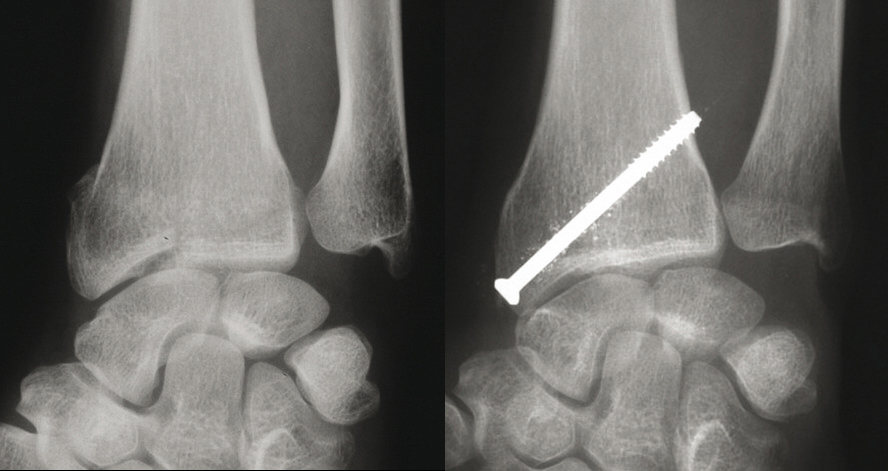

© Guillaume Herzberg, La Revue du Praticien (À gauche) Fracture marginale externe détachant un gros fragment de styloïde radiale.(À droite) Traitement : brochage percutané ou sous contrôle arhtroscopique.